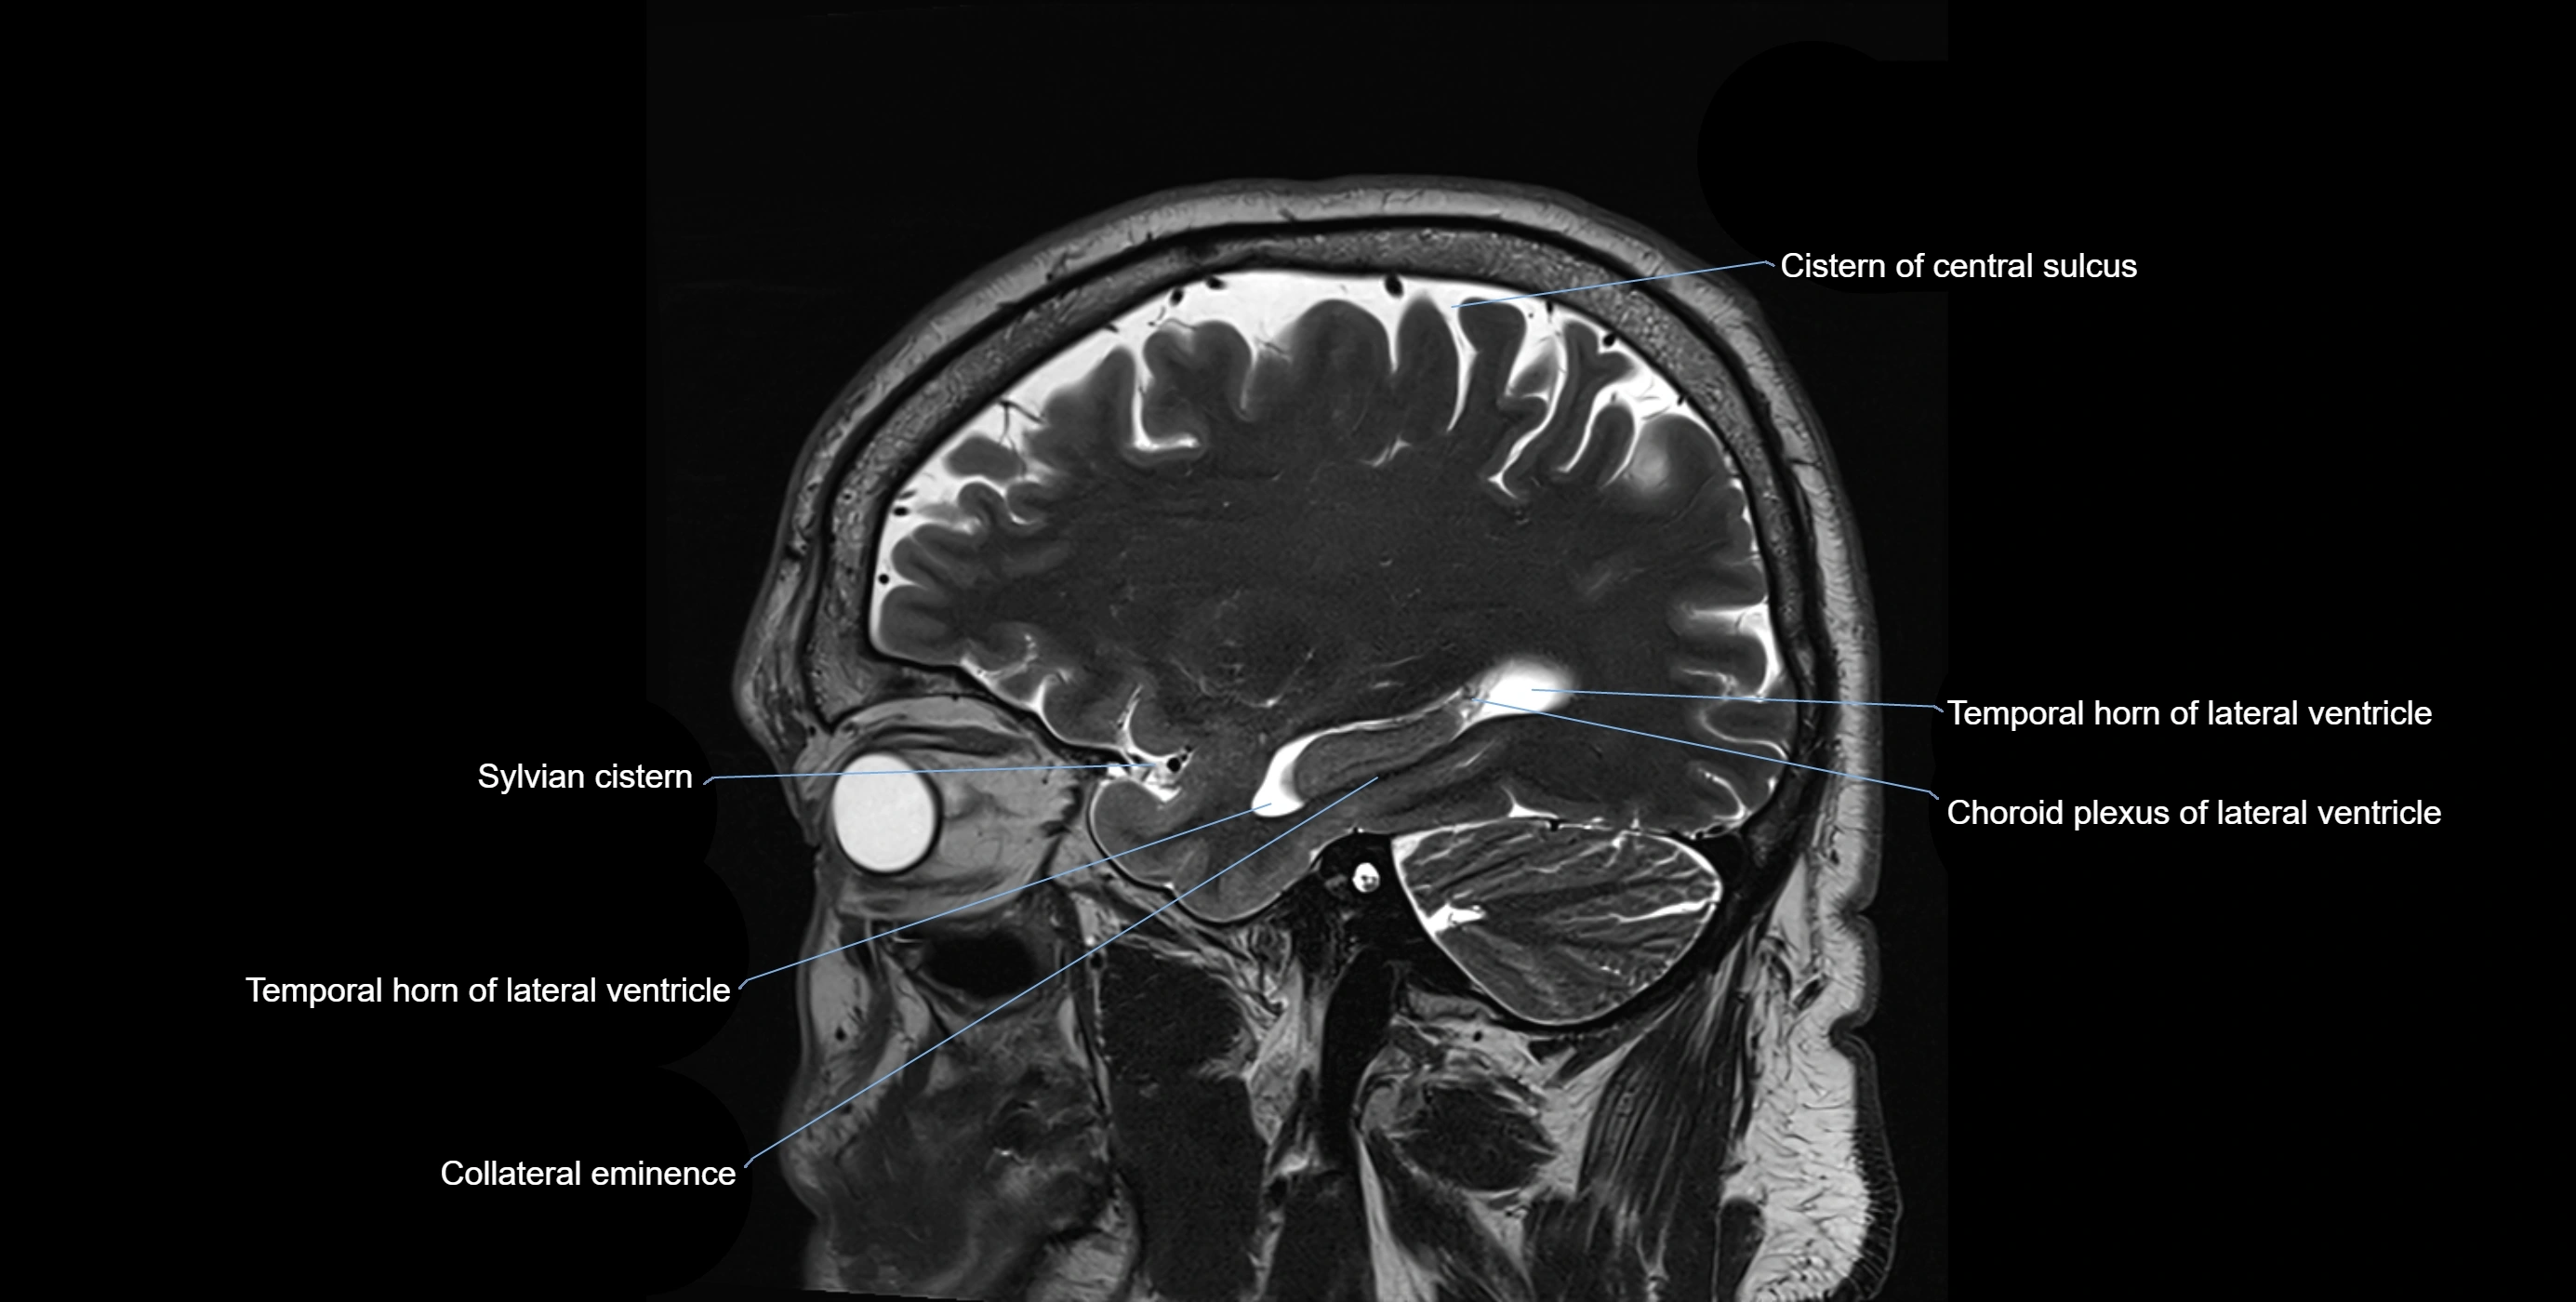

MRI images

image